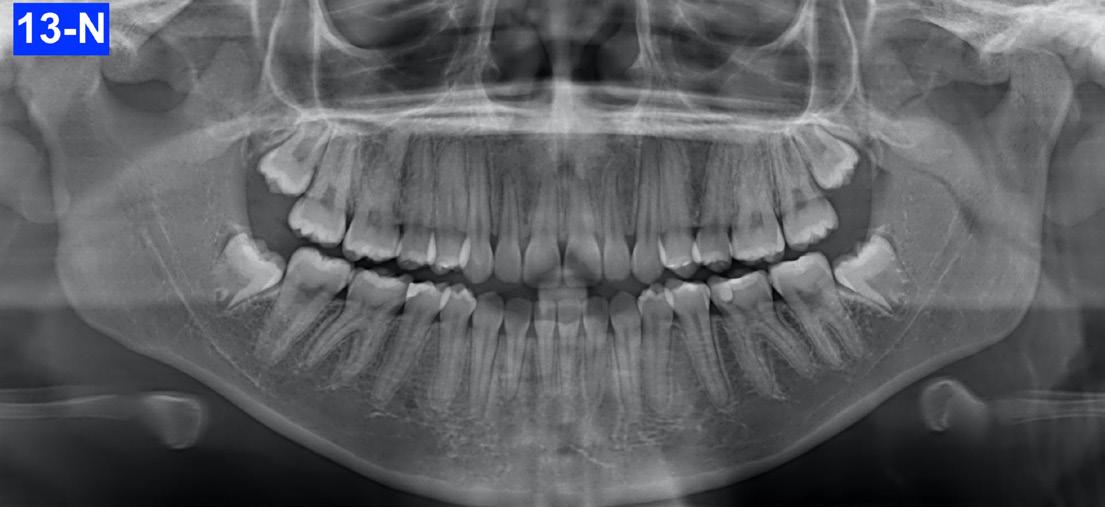

Panoramic radiogram revealed a complete permanent dentition with four impacted wisdom teeth. There was excellent bone support and no signs of periodontal or periapical pathology (Figure 5-A).

Fig. 5-A: Pre-treatment, panoramic radiogram